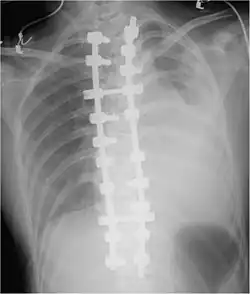

.jpg)